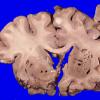

Artifact - Swiss Cheese Brain (3)